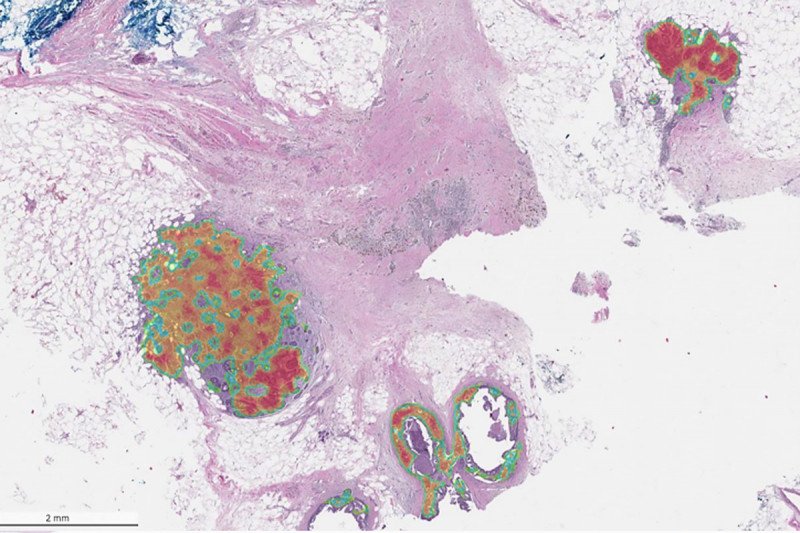

A section of breast tissue with cancerous changes identified.

Shades of red, orange, and green indicate Paige Breast Alpha detection of invasive ductal (middle left, top right) and in-situ (bottom right) carcinoma of the breast.